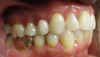

Fig 4. Candidates for hybrid teledentistry include patients with minor (Fig 2), moderate (Fig 3), and advanced crowding (Fig 4).

Figure 4